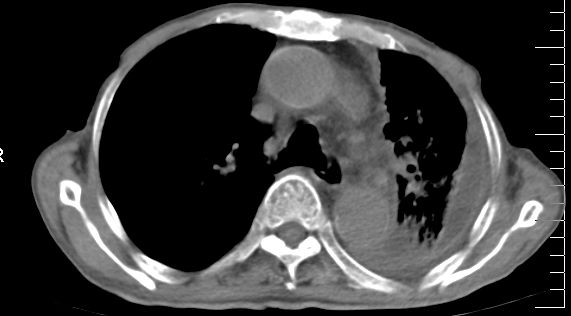

标题: CT10141:男、84岁,咳嗽、咯血1年。 [打印本页]

标题: CT10141:男、84岁,咳嗽、咯血1年。

1左侧胸腔积液并包裹2心包积液3左下肺癌?建议支纤镜检。

支持左侧中央型肺癌伴下叶肺不张\\纵隔淋巴结转移.左侧包裹性胸腔积液\\心包积液.左侧少量胸腔积液..慢性支气管炎伴部分间质纤维化.

咯血病史较长,左肺下叶实变,体积未明显缩小,隐约可见血管影及坏死阴影,双肺门及纵隔淋巴结增大,心包增厚积液,纵隔右移位,单侧胸腔积液,首先考虑:大叶型肺泡癌伴纵隔心包转移。